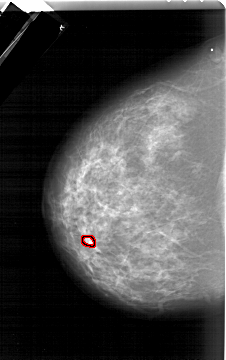

A_1284_1.LEFT_MLO

FILE: A_1284_1.LEFT_MLO.OVERLAY

TOTAL_ABNORMALITIES 1

ABNORMALITY 1

LESION_TYPE MASS SHAPE OVAL MARGINS OBSCURED

ASSESSMENT 4

SUBTLETY 3

PATHOLOGY BENIGN

TOTAL_OUTLINES 1

BOUNDARY